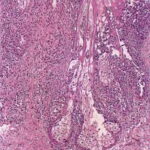

Histopathology. In Ofuji’s disease, there is exocytosis of eosinophils into a spongiotic follicular infundibulum and accompanying sebaceous gland, eventually forming eosinophilic micropustules . The epidermis adjacent to the affected follicle may contain lymphocytes and eosinophils, with the latter aggregating into small eosinophilic pustules that are subcorneal or intraepidermal; these epidermal changes reflect the histologic picture seen in palmoplantar lesions, where follicles are absent . In more inflamed lesions neutrophils may be present . In the dermis, there are perivascular and interstitial infiltrates of lymphocytes and numerous eosinophils, which may surround sweat glands. Associated follicular mucinosis has been reported . |

A study of 52 biopsies in 50 HIV-positive patients best described the histology of HIV-associated eosinophilic folliculitis . Perifollicular and intrafollicular lymphocytes and eosinophils are concentrated about the isthmus, and may involve the sebaceous duct. There is spongiosis of the follicular epithelium. Eosinophils and lymphocytes may be seen aggregating in the hair canal, but neutrophils are rare. In early lesions, lymphocytes may predominate and be distributed perifollicularly and interstitially. In more developed lesions, dermal inflammation diminishes and perifollicular/follicular inflammation increases. Less common findings include inflammation of the sebaceous gland, eosinophilic pustules, and follicular rupture (128). Dense eosinophilic infiltrates with degranulation and flame figures, resembling Well’s syndrome, may sometimes be seen. A small number of macrophages can be present. Bacteria, yeast, or Demodex may be identified, albeit away from the areas of inflammation. Because the disorder is highly pruritic, excoriation is a common secondary finding. |